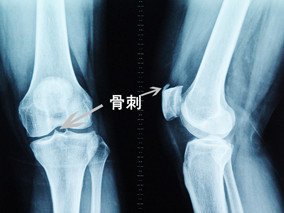

很多人因为膝关节疼痛而就诊,在医院的检查中会发现关节内长了骨刺,大家很迷惑的一个问题是:疼痛是骨刺引起的吗?去掉骨刺后我的关节是否就可以不疼痛了?

虽然骨刺是医生诊断骨性关节炎的一个依据,但绝大多数不是引起局部疼痛的真正原因,更不是它直接引起疼痛症状。只有当局部的骨刺对周围的软组织产生顶压等刺激时,才会引起局部的疼痛症状,并且这种情况非常少见。

一般来讲,疼痛是由于关节内存在炎症,并非是存在的骨刺在起作用。所以单纯去掉骨刺并不能解决关节的疼痛问题,也不能解决关节炎问题。希望大家不要再轻信那些声称可以“消除骨刺”的药物或者可以“切除骨刺”的手术,这也是针对老年性退变性膝关节炎采用膝关节镜进行关节清理手术后效果不好的根本原因。